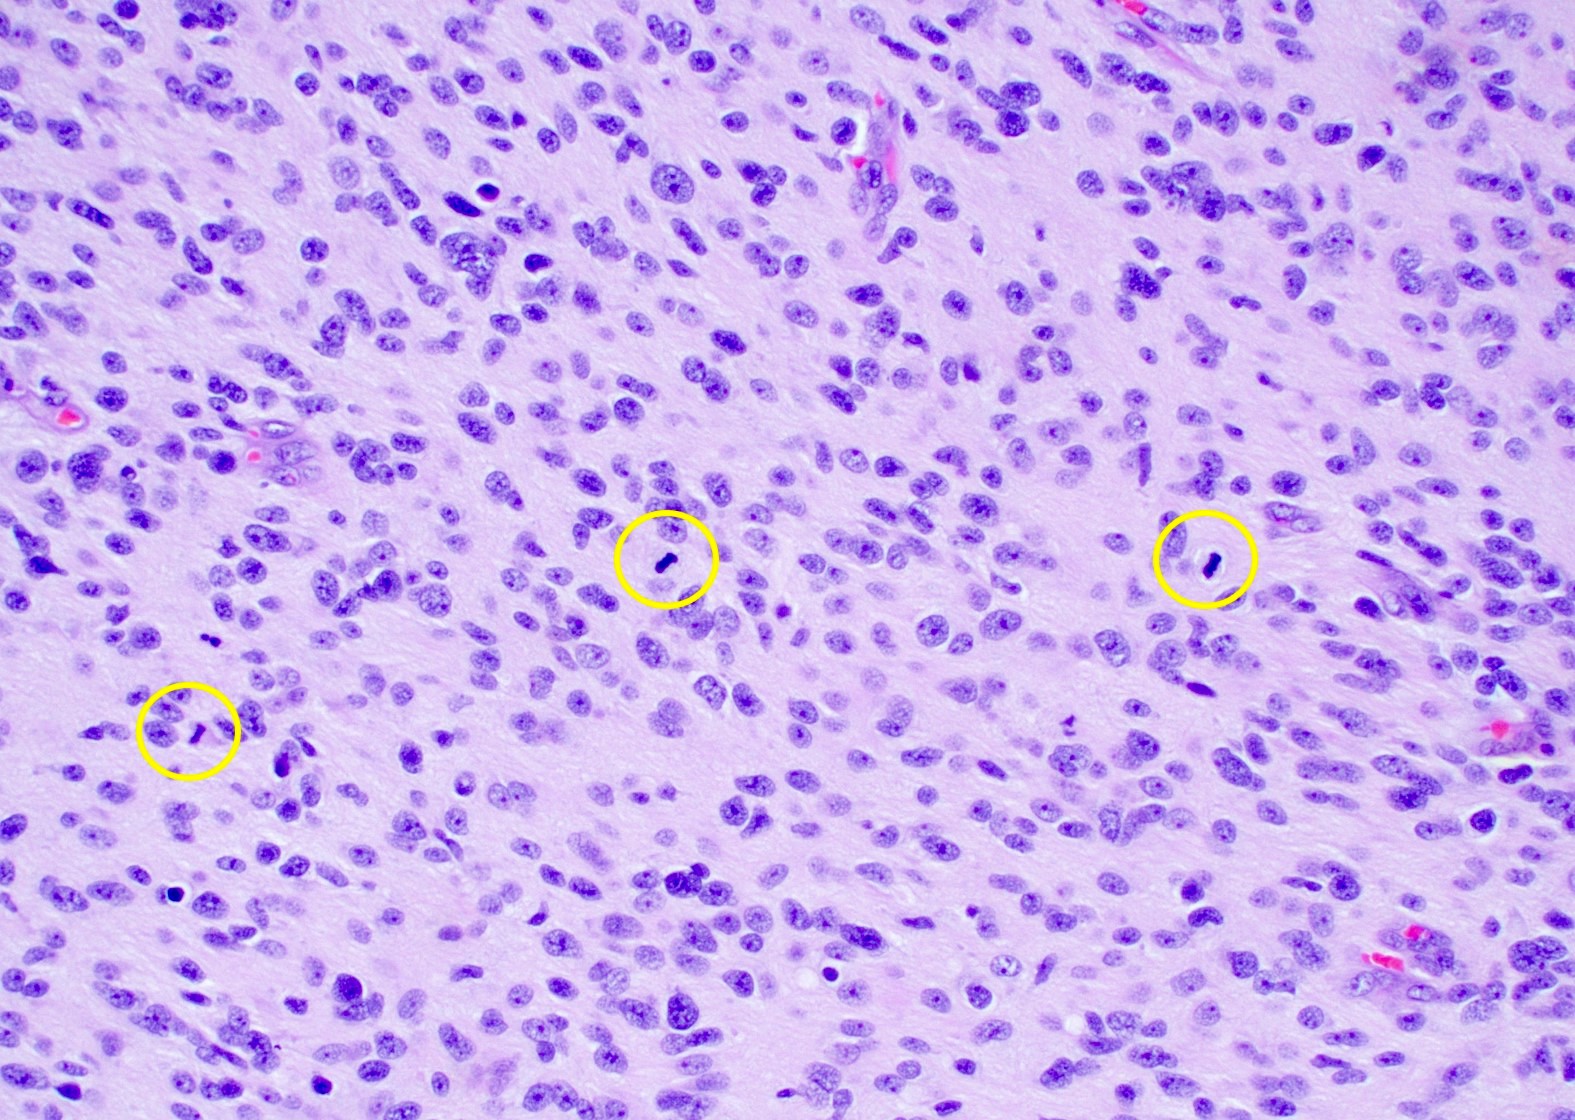

Microscopic (histologic) description

- Infiltrating, hypercellular astrocytic neoplasm often with hyperchromatic, elongated nuclei and irregular nuclear membranes

- Typically mitotically active, though not required if molecular criteria are met

- Microvascular proliferation or necrosis is required for a histologic diagnosis of GBM

- Microvascular proliferation: multilayered, small caliber vessels with glomeruloid appearance (J Neuropathol Exp Neurol 1992;51:488)

- Necrosis: can be geographic or pseudopalisading with neoplastic cells surrounding central necrosis

- Small cell change: monomorphic cells with small, round or angulated, hyperchromatic nuclei and brisk mitotic activity

- Associated with EGFR amplification (Clin Neuropathol 2005;24:163, J Neuropathol Exp Neurol 2001;60:1099)

Microscopic (histologic) images

Contributed by Bharat Ramlal, M.D. and Meaghan Morris, M.D., Ph.D.